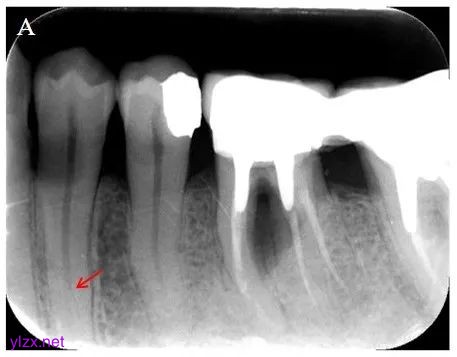

影像学检查:X线示34牙冠部中份见牙体组织低密度影;根尖区未摄及,提示工作长度较长;根管中下段可见粗大根管影像分为两条细小分叉,提示根管中下段分为颊侧、舌侧根管(图1A)。

图1A 患者治疗前影像学检查结果(2024-09):X线片示颊侧、舌侧根管通路分离(箭头)